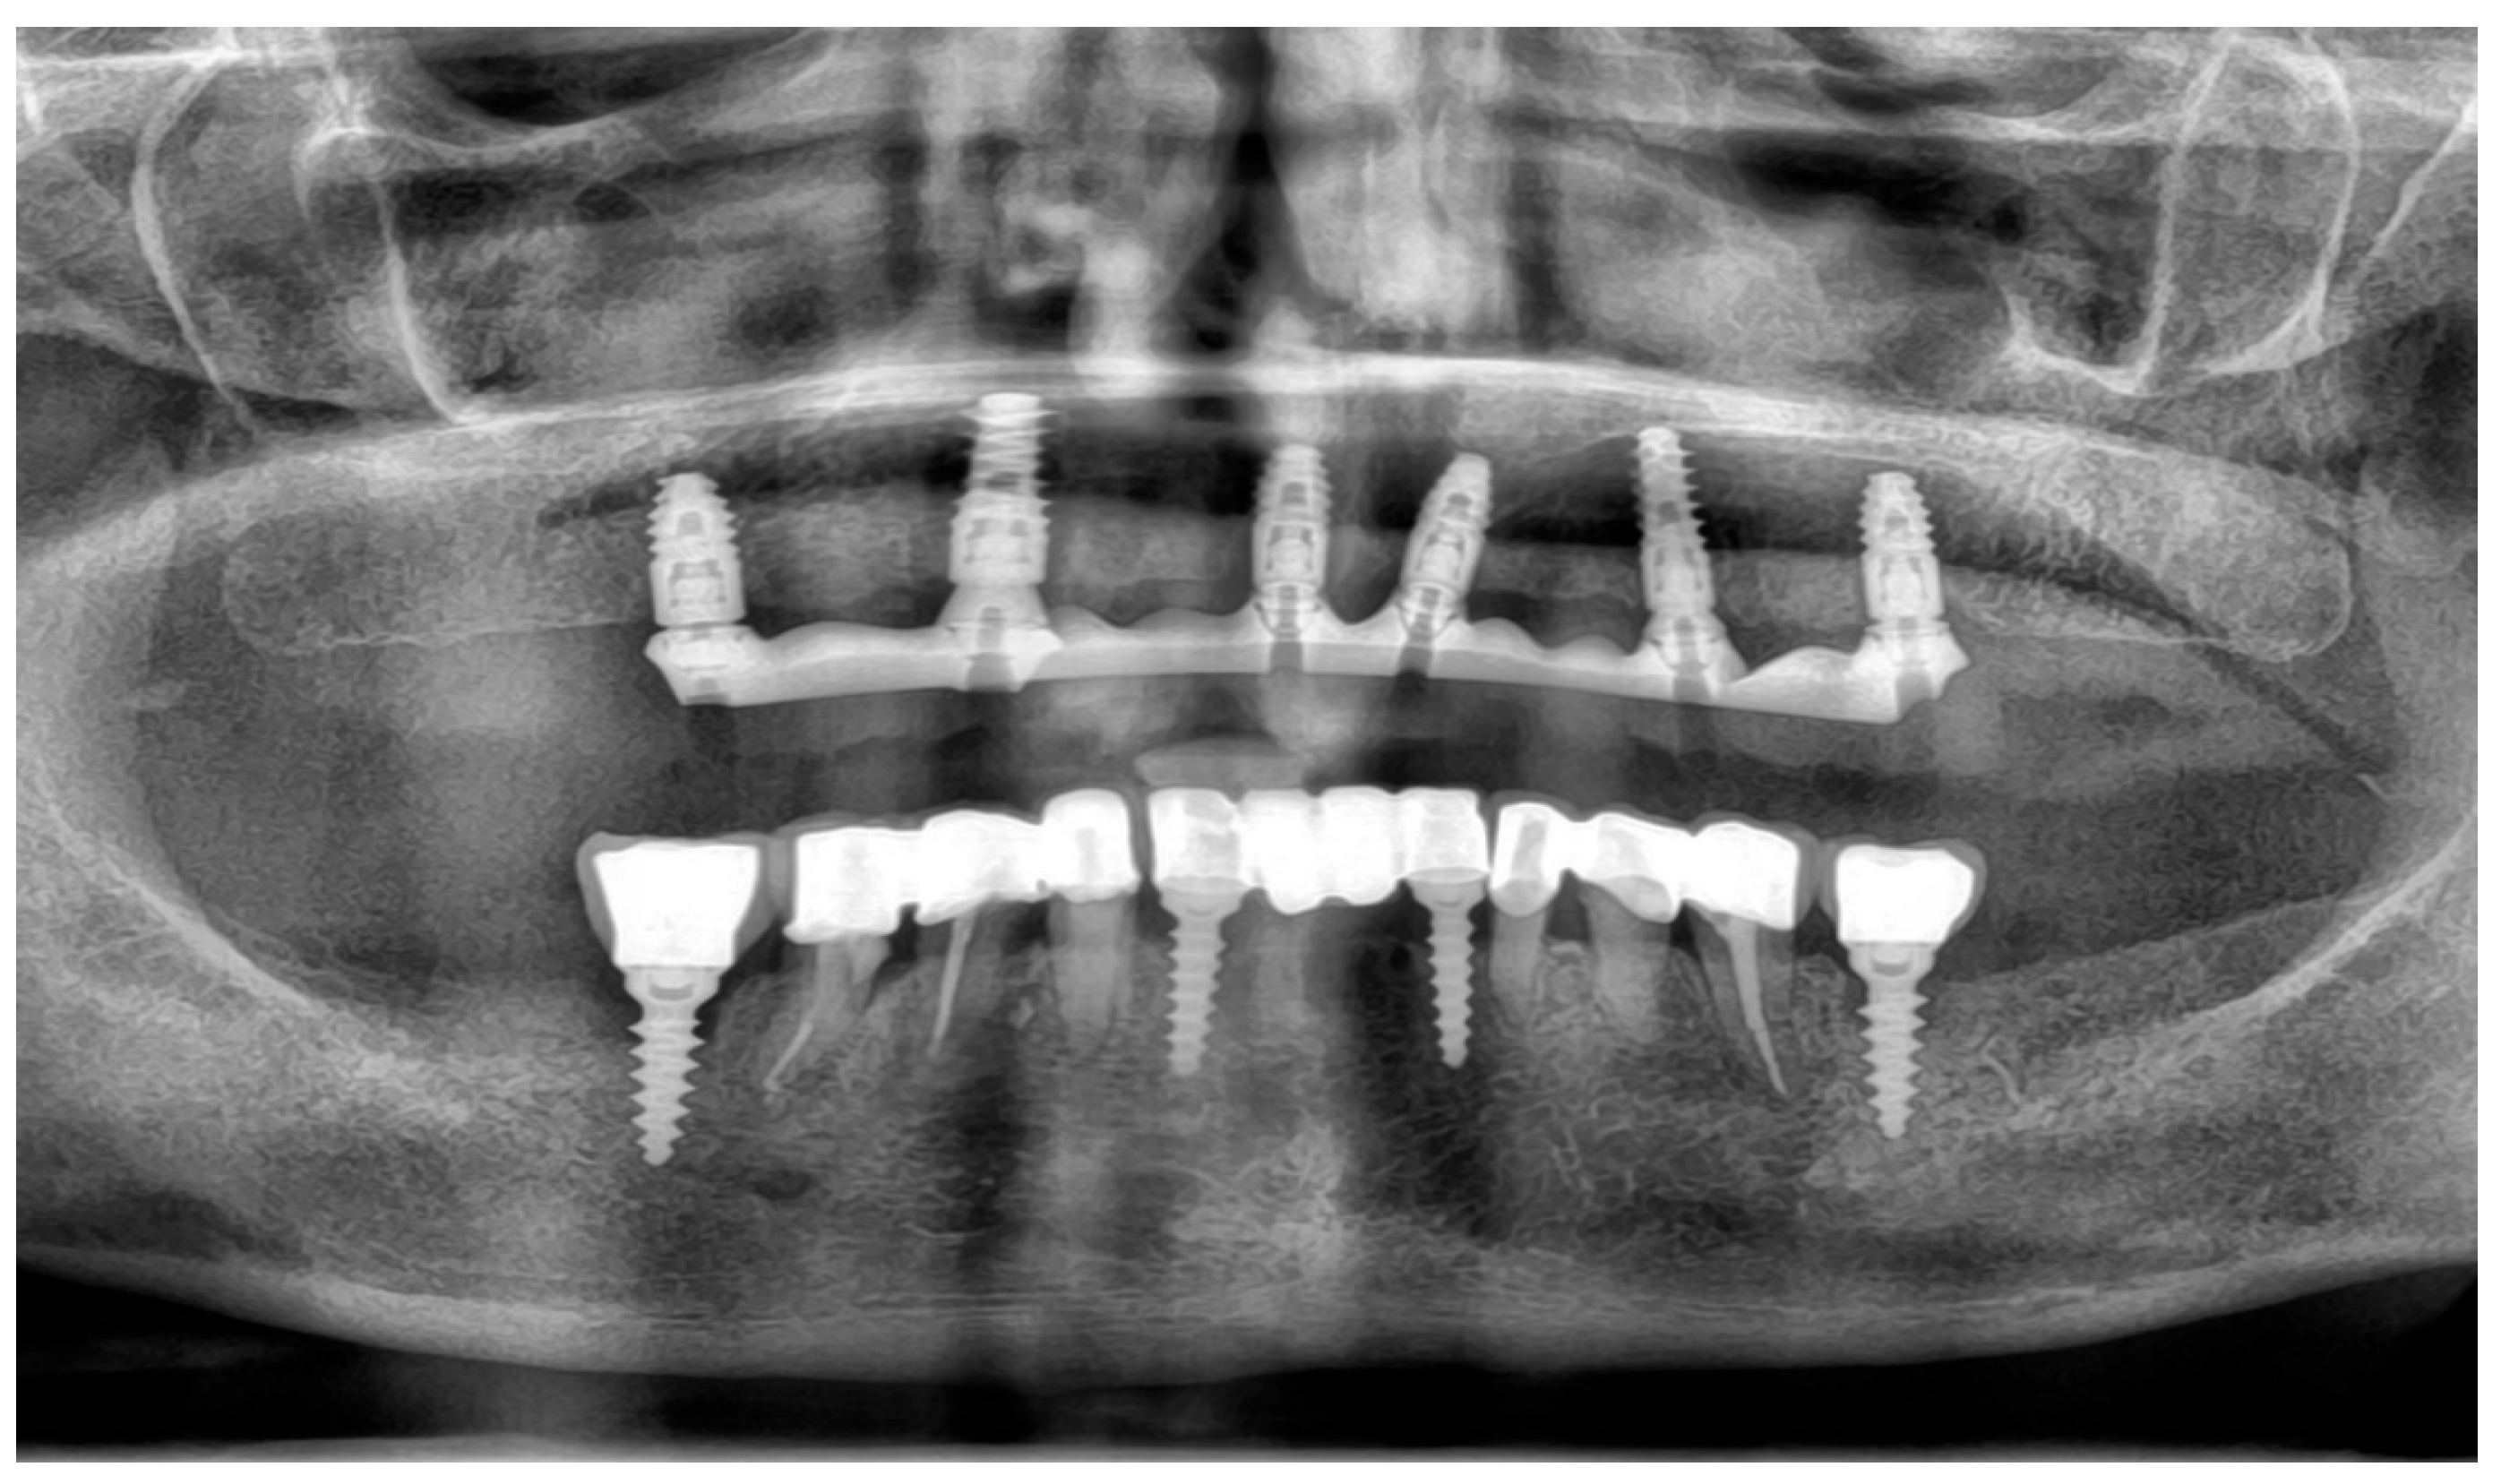

Clinical examination revealed stable and functional restorations in the lower arch. A 4-unit implant-supported bridge was present, supported by two implants in positions 32 and 42. Positions 33–35 and 43–45 were prosthetically reconstructed with tooth-supported blocked crowns fixed on each tooth, respectively. Single implant-supported crowns were present in positions 36 and 46, both in good condition. The patient reported no complaints regarding the mandibular reconstructions.

In the upper arch, a 4-unit implant-supported bridge was present in the anterior region, supported by implants in positions 11 and 21, with cantilevers extending to 12 and 22. Segments 23–25 were restored with tooth-supported blocked crowns on teeth 23, 24, and 25. Segments 13–15 were reconstructed with a tooth-supported bridge anchored on teeth 13 and 14, with a distal cantilever in position 15. Additionally, two single implant-supported crowns were located at sites 16 and 26. The clinical evaluation of the peri-implant soft tissues surrounding the previously placed implants revealed favourable conditions, with no signs of inflammation or peri-implant defects. Based on the patient’s records and clinical inspection, the existing implants in the maxilla were identified as ICX implants (diameter 4.1 mm, length 10 mm) (ICX-Implant System; Medentis Medical GmbH, Bad Neuenahr-Ahrweiler, Germany).

To supplement the clinical findings, a cone beam computed tomography (CBCT) scan was obtained (Figure 1) and evaluated. The implants existing in the maxilla demonstrated proper surrounding bone architecture. The compromised status of the remaining teeth was confirmed. In addition, the available bone conditions in the regions of teeth 14 and 24 were assessed to be adequate for future implant placement, particularly in the context of immediate implant insertion. This is in accordance with the literature emphasising that sufficient bone volume, labial plate integrity, and socket morphology, are critical prerequisites for successful immediate implant placement [7,8,9].

To verify the implant positions and the accuracy of the prosthetic fit, a control CBCT scan was obtained after the delivery of the early provisional restoration. Radiological evaluation confirmed stable positioning of the implants and correct seating of the prosthesis (Figure 11 and Figure 12).

The definitive prosthesis was delivered to the patient after laboratory verification. Intraoral evaluation confirmed accurate seating, passive fit, and proper occlusal relationships. Phonetics and aesthetics were reassessed and found to be satisfactory, consistent with previous retrospective data showing high survival rates and patient satisfaction with zirconia-based full-arch prostheses [28]. A panoramic radiograph was obtained at the time of prosthesis delivery to confirm the correct seating of the framework–zirconia assembly on all supporting implants, as well as to verify stable peri-implant bone conditions.

Figure 1. Preoperative panoramic reconstruction from CBCT, showing the initial condition of the existing tooth- and implant-supported restorations in the maxilla and mandible, as well as the visualisation of two planned implants in positions 14 and 24.

Figure 11. Control CBCT scan obtained after the delivery of the early full-arch provisional restoration.

Figure 12. Control CBCT scan obtained after the delivery of the early full-arch provisional restoration.